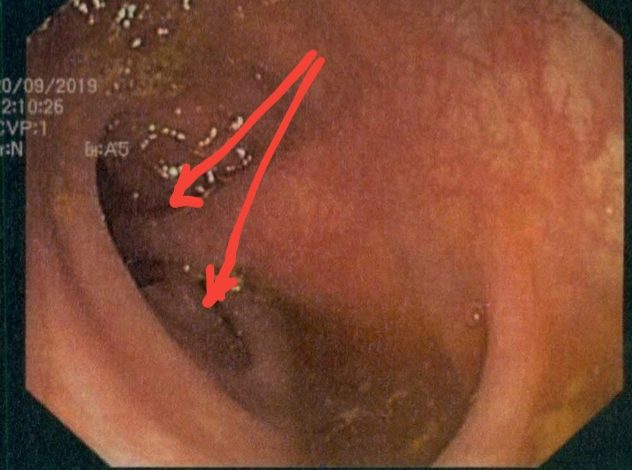

Άλλες παθήσεις σκωληκοειδούς απόφυσης. Αδένωμα. Βλεννοκήλη. Ψευδομύξωμα. Καρκινοειδές. Άλλες παθήσεις της σκωληκοειδούς απόφυσης εκτός από την οξεία σκωληκοειδίτιδα Άλλες παθήσεις που αφορούν τη σκωληκοειδή απόφυση και μπορούν να εκδηλωθούν με οξεία σκωληκοειδίτιδα ή και τυχαία κατά τη διάρκεια σκωληκοειδεκτομής είναι οι ακόλουθες: Για τη σκωληκοειδίτιδα, τα αίτια , τα συμπτώματα και τη λαπαροσκοπική σκωληκοειδεκτομή , […]